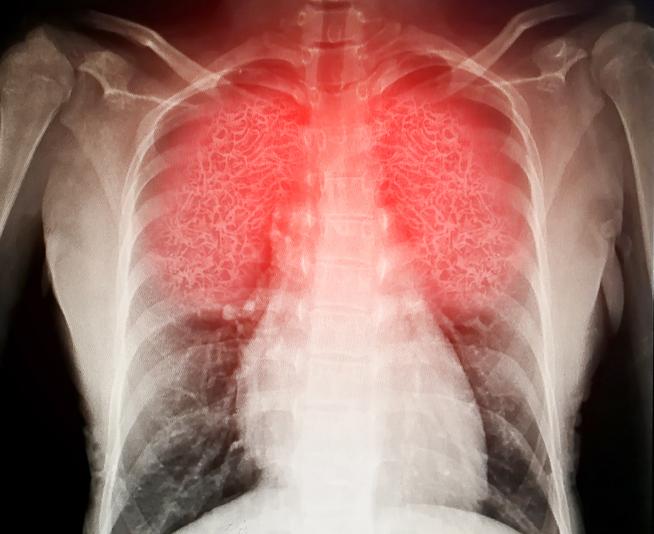

Das Schwere Akute Respiratorische Syndrom (SARS) und das Middle East Respiratory Syndrom (MERS) sind Virusinfektionen. Beide Infektionen können sehr schwerwiegende Krankheiten verursachen, die vor allem die Lunge betreffen.

Das zweite Stadium betrifft die Lunge und beginnt drei Tage oder mehr nach Beginn der Symptome. Es kommt zu einem trockenen Husten, meist ohne Schleim, Fieber und Atemnot. Der Husten variiert von leicht bis schwer.

MERS werden Sie für Tests (Untersuchungen) ins Krankenhaus eingewiesen. Zu diesen Tests gehören Blutuntersuchungen und eine Röntgenaufnahme des Brustkorbs. Möglicherweise ist auch eine Computertomografie (CT) des Brustkorbs erforderlich.